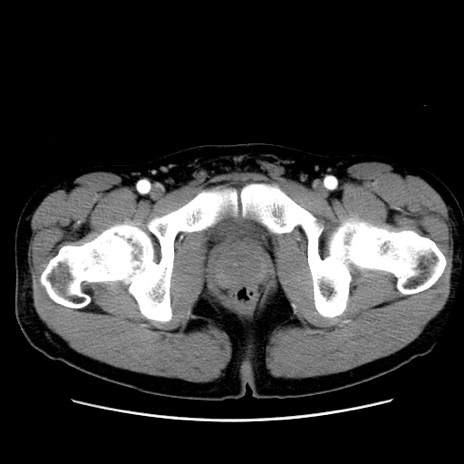

症例36(横断像)

【症例】20歳代 男性

【主訴】心窩部痛

【現病歴】今朝より上腹部痛あり。一旦軽快していたが再度出現したため救急要請。昨日夕に白身の魚を含む刺身を食べた。

【身体所見】BP 136/89mmHg、HR 74/min、BT 37.0℃、腹部:膨満、軟、心窩部に圧痛あり。反跳痛なし、筋性防御なし、腸雑音やや亢進あり。

【データ】WBC 17700、CRP 0.48